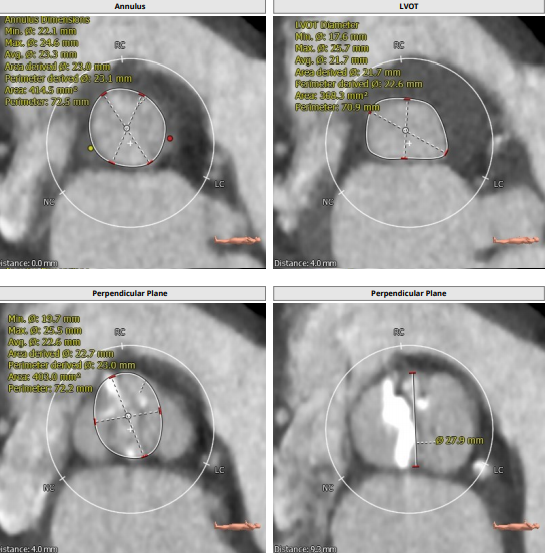

此例患者大横位Type0型二叶瓣,瓣环径23.1,LVOT22.6,Stj35.9,左冠高度11.8,右冠19.5,术前根据总体结构使用20MM球囊预扩,抓捕器辅助瓣膜通过横位结构跨瓣,术前预装VenusA23号瓣膜。

根部解剖: